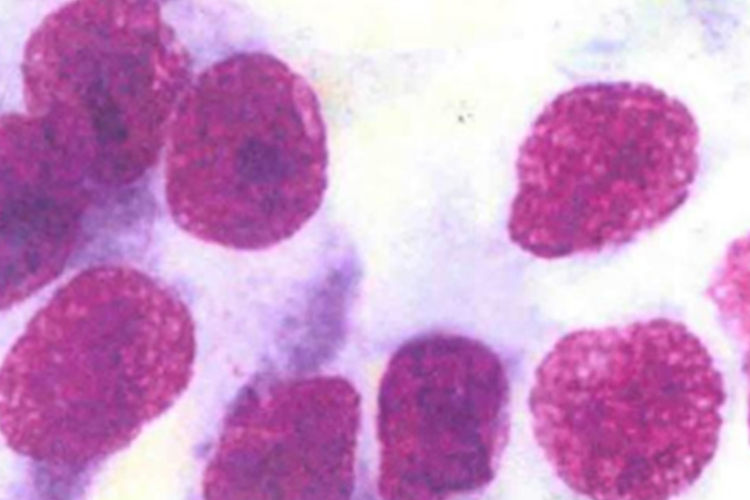

高分化腺癌:胞体较大,大小不一,呈圆形、卵圆形,形态异形不明显,胞质丰富,可含有空泡,有时空泡将胞核挤于一侧,形成印戒样癌细胞;与鳞癌相比,核大、核畸形、核深染不明显。